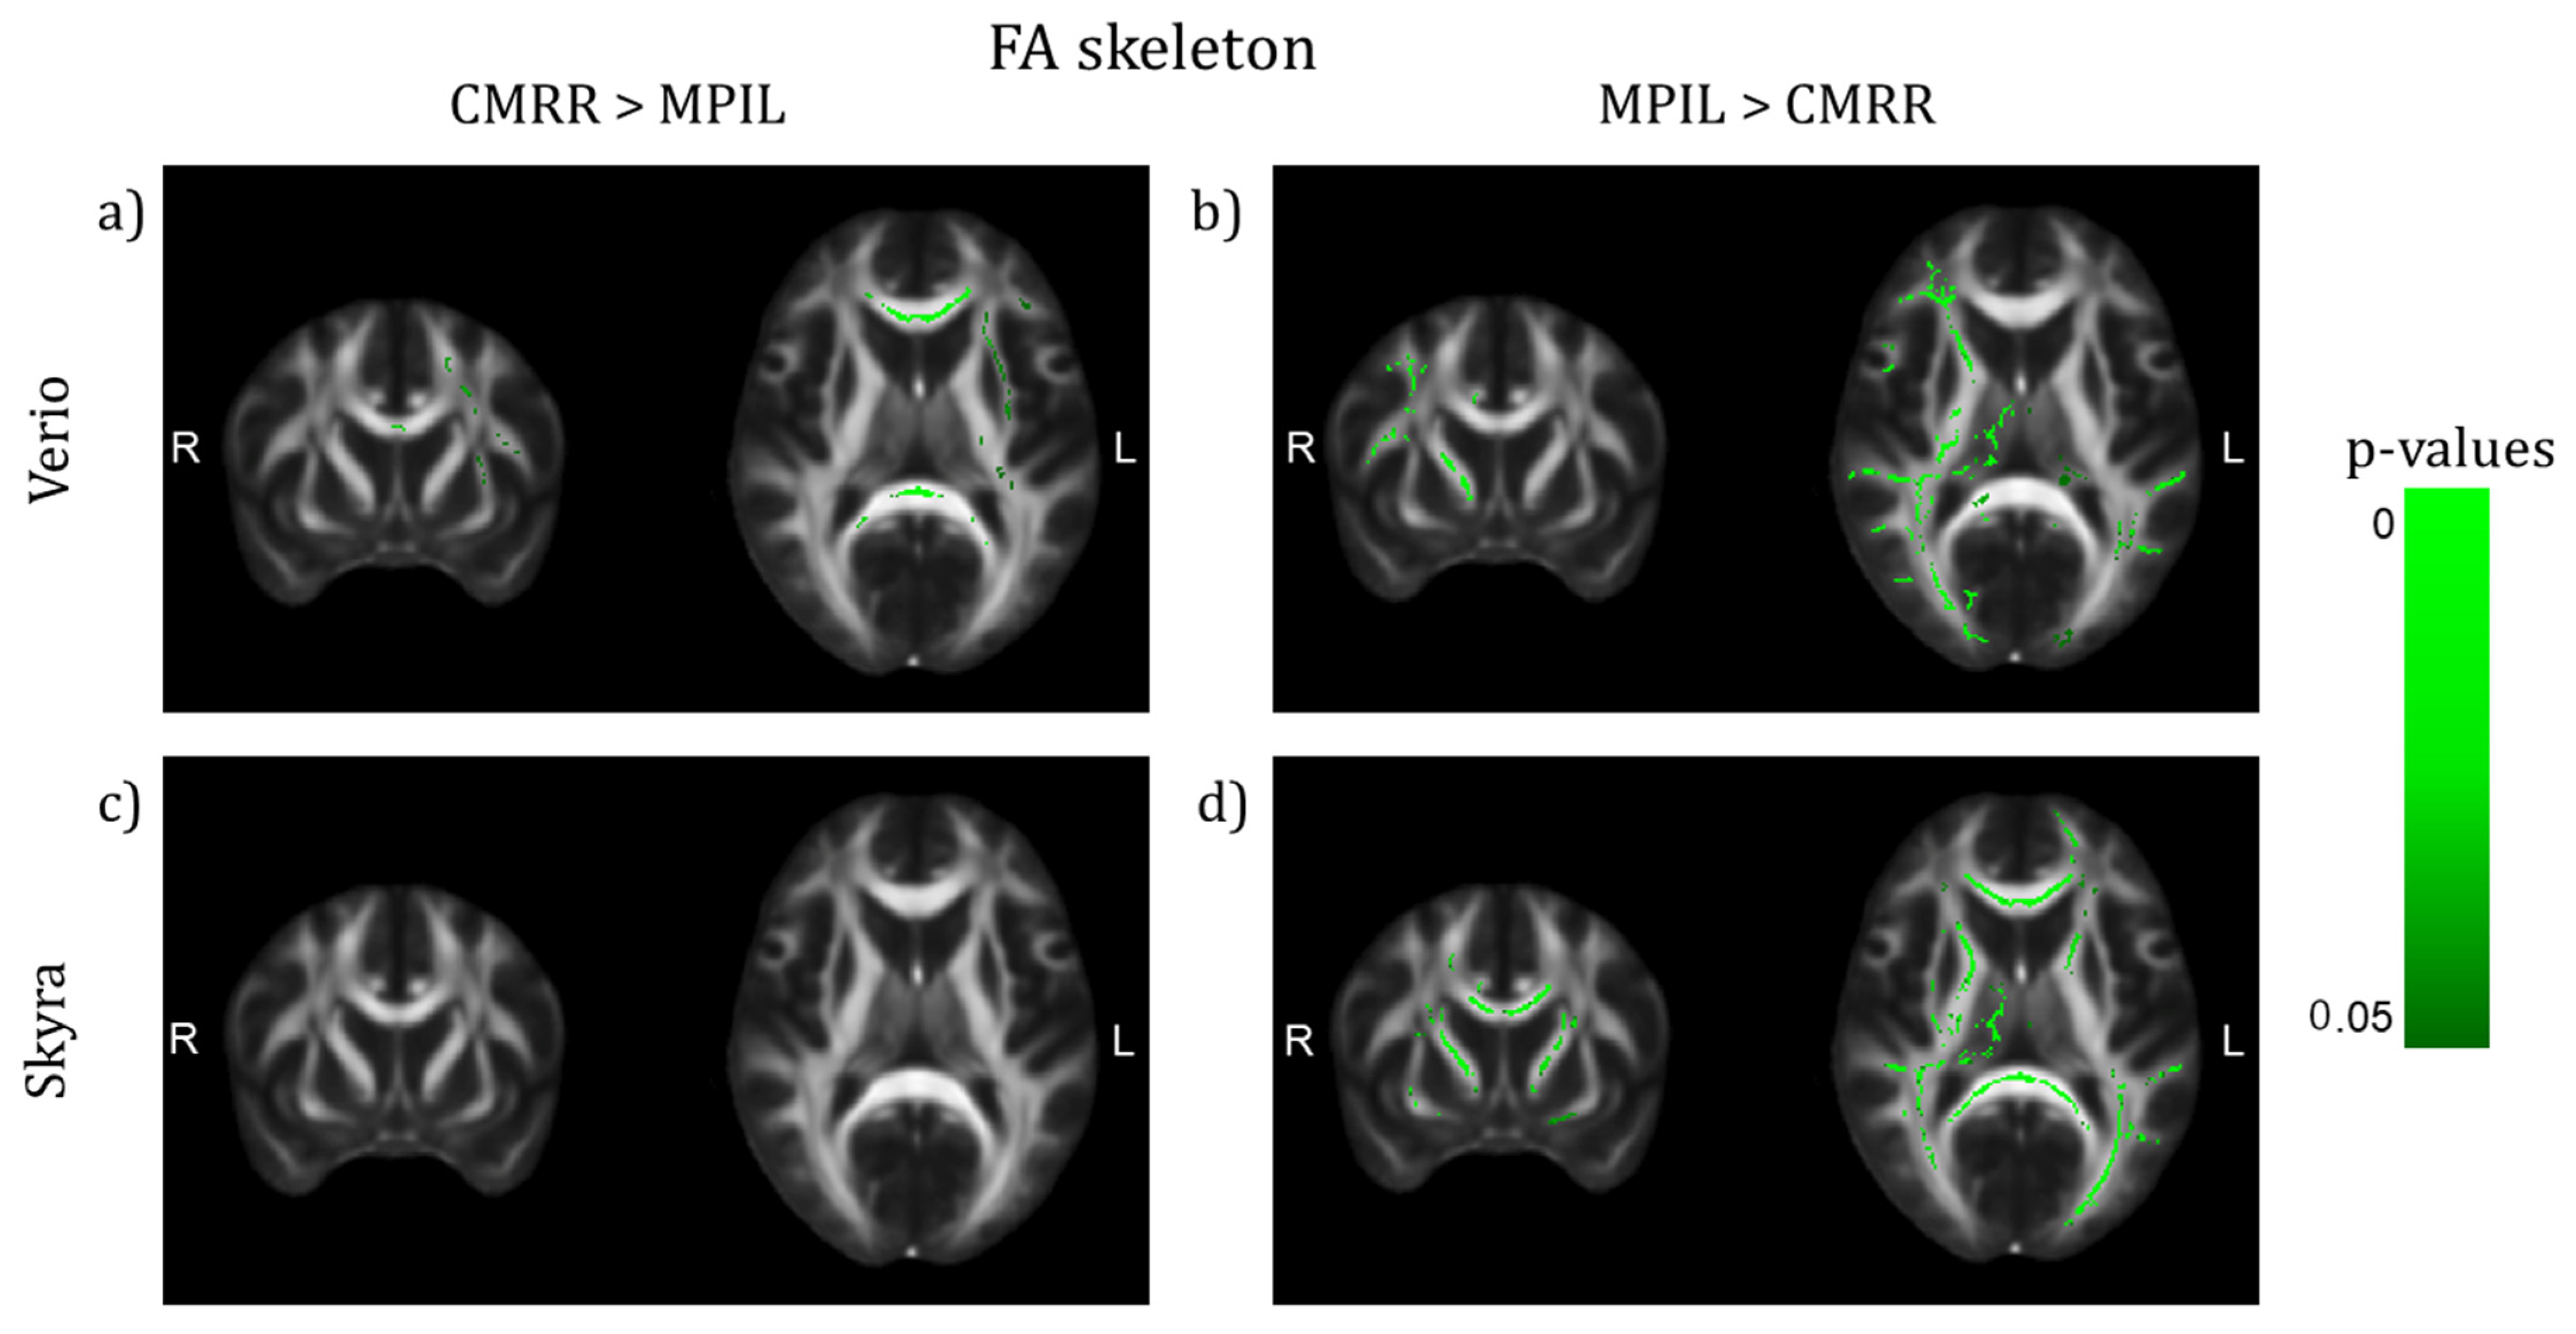

θcomplex3 eYecandy vs. θcomplex Same Brain, Different Look?—The Impact of Scanner, Sequenceの詳細情報

Same Brain, Different Look?—The Impact of Scanner, Sequence。Amazon.com: TheraSuva Total Eye Complex - Lutein + Bilberry。Comparing 3D, 2.5D, and 2D Approaches to Brain Image Auto。★プロフィールを一読下さい★・ぱんしょこと申します。アニメゲーム同人系CDを多数出品しています。よろしければフォローお願いいたします。・即購入→全商品可能です。・値下げ→全商品可能です。※一部例外あり★状態★・本商品についての状態は下記矢印以降に記入しております。→本商品はディスク面に目立った傷等なく、問題なく再生可能です。・当方出品物は当方がパソコンにて取り込みをしております。※ 動作確認は取り込み時に行っておりますので、CD再生は全商品可能となっております。・CDケースの状態につきましては、状態の記載に反映されておりません。※CDのディスク状態が反映されております。・商品の記載事項については、同一文面を使用しておりますため、少しでも気になる事がございましたら、必ずご質問くださいませ。例)ケース状態、商品付属物、ブックレート状態帯の有無、特典の有無、見にくい箇所など・全商品にテンプレート文章が反映されております※写真に写っている物のみが販売物となります。・下記ハッシュタグより当方出品CDのみがご覧いただけます。→ #ZAINのアニメCD達。Same Brain, Different Look?—The Impact of Scanner, Sequence。けむけむ (詳細コメント欄)。【新品未開封】Liella Club プレミアム盤 CD BD3枚 継続特典付。「強殖装甲ガイバー・スペシャル」 2枚組CD 初期OVA版のサントラです。ゾイドオリジナルサウンドトラック。THAT'S ATARI MUSIC ATARI GAMES 1 ゲームサントラ。遊戯王 SOUND DUEL~QUARTER CENTURY SELECTION。【CD】「怪盗セイント・テール」オリジナル・サウンドトラック/ソングコレクション。「遙かなる時空(とき)の中で5&6」ヴォーカルコンプリートBOX。ミュージカル『刀剣乱舞』 江 おん すていじ ~新編 里見八犬伝~。未開封 けいおん! ! 劇中歌集 放課後ティータイム II 初回限定盤 まとめ。バイク映画プライドワン サントラCD るびいさん専用。【初回プレス特典 封入】トゲナシトゲアリ 新品未開封CD。すたばこ! 「パック・イン・ミュージック」金曜ナチチャコパック傑作集…